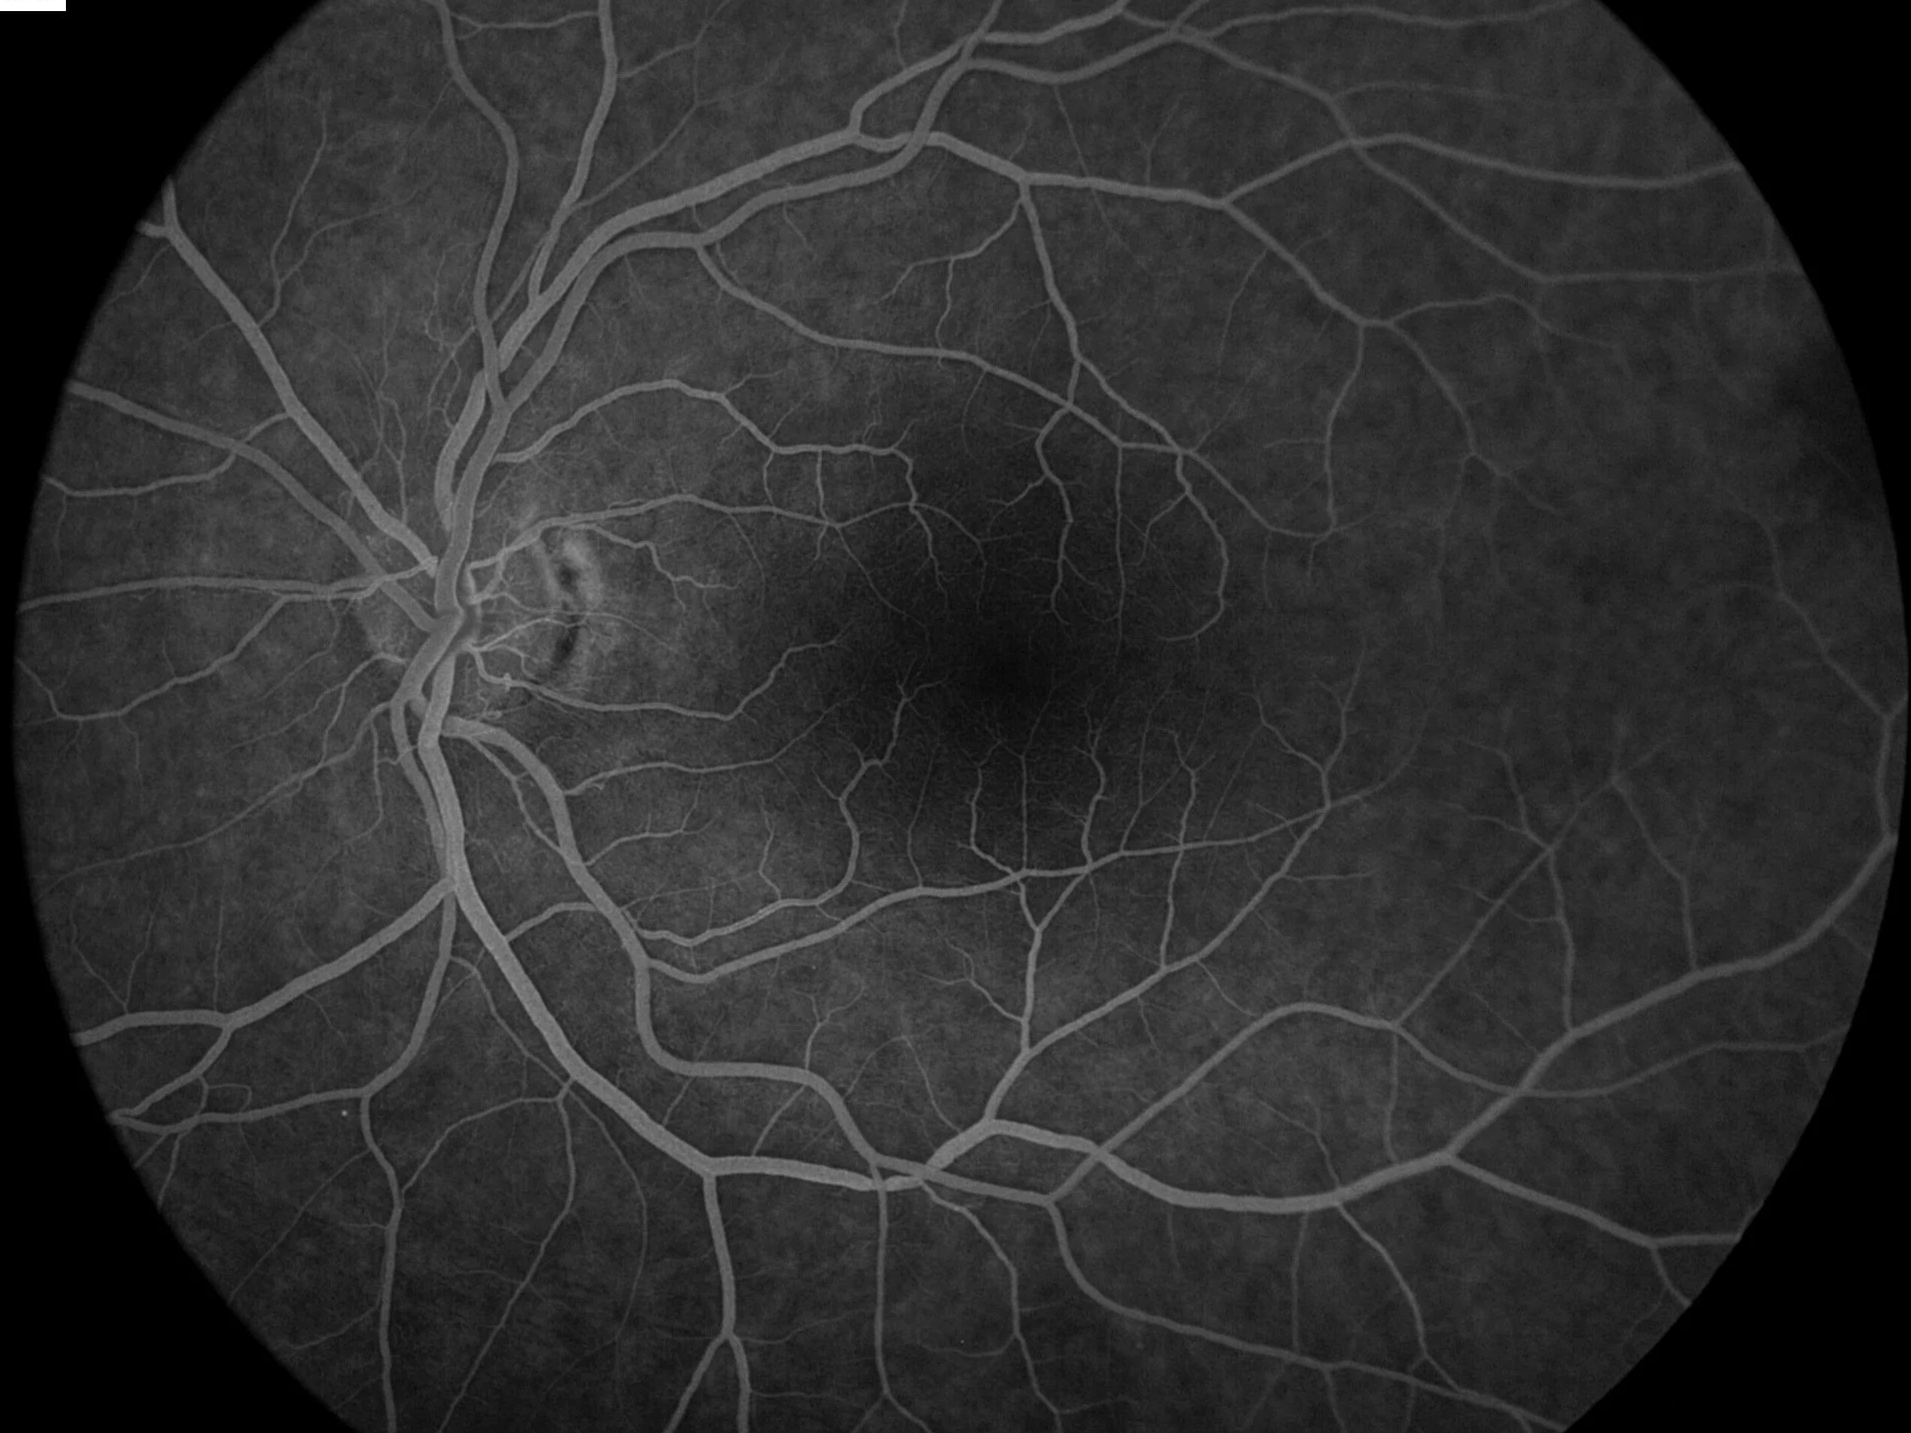

Τι περιλαμβάνει ο έλεγχος: Βυθοσκόπηση με μυδρίαση — OCT για ανίχνευση οιδήματος ωχράς — Σε ορισμένες περιπτώσεις: Angio-OCT ή φλουοροαγγειογραφία